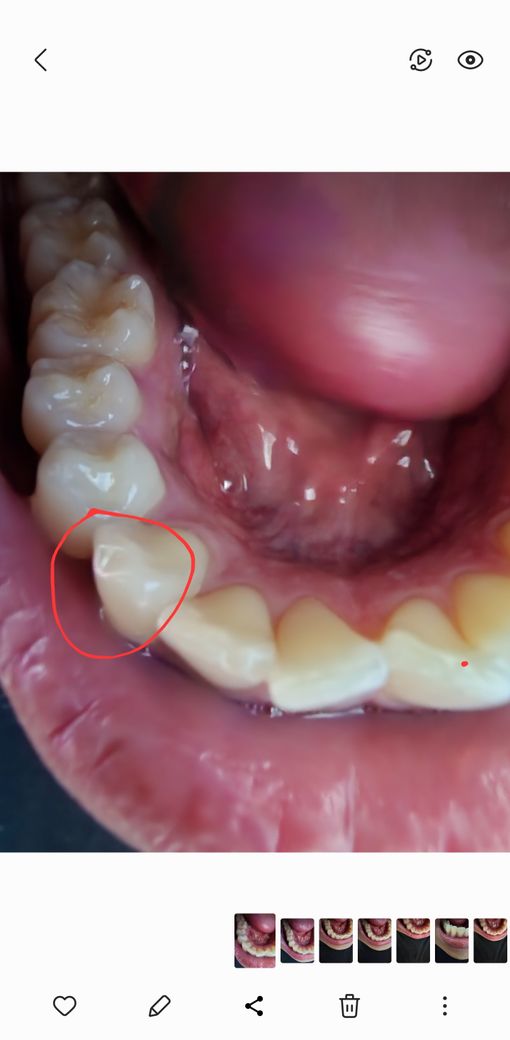

쇠젓가락을 씹어서 이가 깨졌는데요

오늘 치과를 가서 검사를 받으니 스크래치난 부분도 없고

깨진 부분은 딱히 이상 없다고 그냥 써도 된다는데

계속 쓸 경우 깨진부위가

닳아서 갈리거나 그럴 수도 있나요?